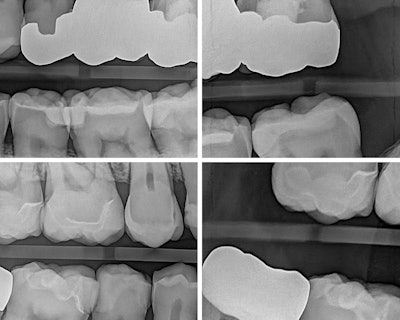

In my own practice, I compared two bitewings from the same patient, one taken with Acuity and one with our existing sensor, using identical exposure settings. The Acuity image immediately stood out. It showed noticeably sharper definition, cleaner contrast, and clearer interproximal visibility. The improvement was visible at a glance and reinforced the diagnostic advantages reported by our evaluators. This kind of image sharpness saves time and reduces retakes.

Figure 2: Four identical bitewings, same exposure, taken from the same patient using another intraoral sensor.Dr. Chris Catalano.